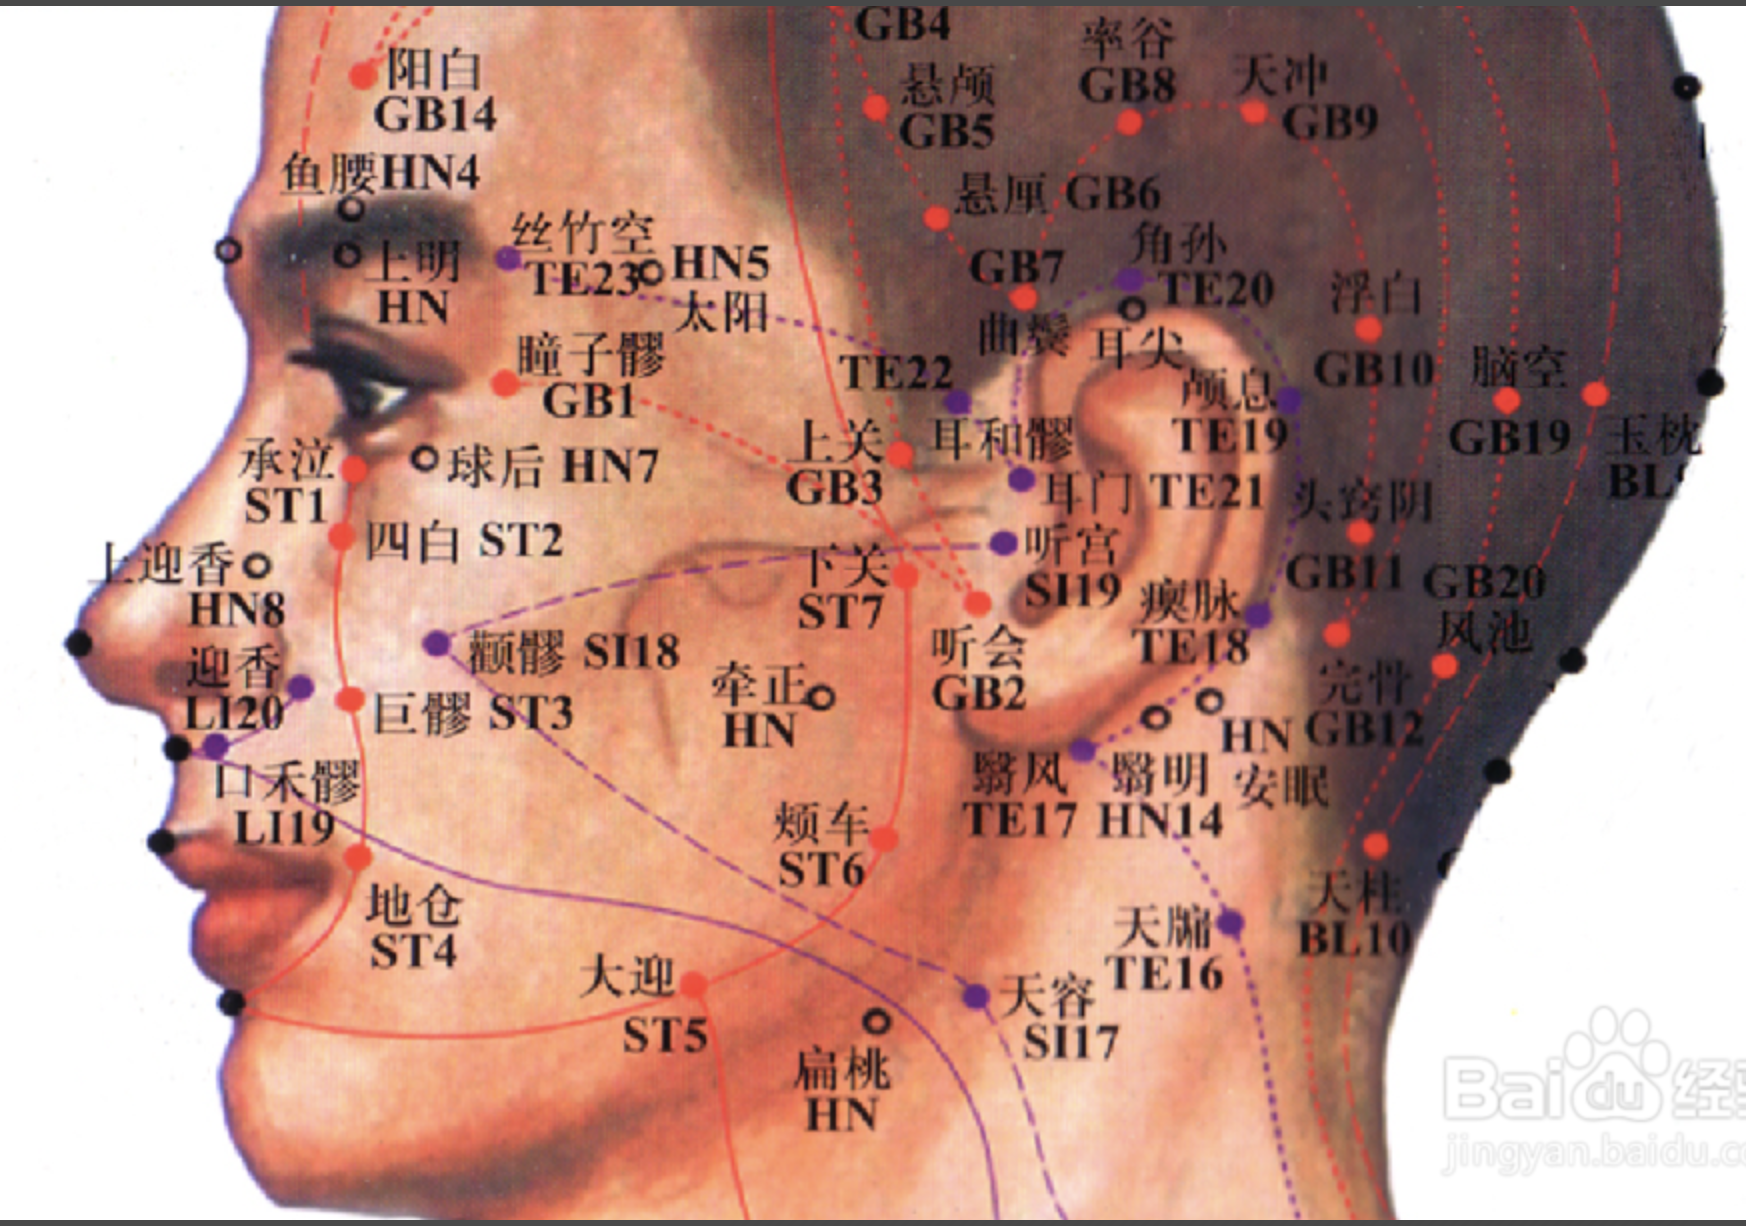

【(三)足阳明胃经(图10-21-1)】

图 10-21-1 足阳明胃经循行及常用腧穴

2、歌诀 四十五穴足阳明,承泣四白巨髎(liáo)经,地仓大迎下颊车,下关头维对人迎,水突气舍连缺盆,气户库房屋翳寻,膺窗乳中下乳根,不容承满出梁门,关门太乙滑肉起,天枢外陵大巨里,水道归来达气冲,髀关伏兔走阴市,梁丘犊鼻足三里,上巨虚连条口底,下巨虚下有丰隆,解溪冲阳陷谷同,内庭厉兑阳明穴,大趾次趾之端终。

3、经脉循行 起于鼻翼两侧(迎香),上行到鼻根部与足太阳经交会,向下沿鼻外侧进入上齿龈内,回出环绕口唇,向下交会于颏(kē)唇沟承浆处,再向后沿口腮后下方,出于下颌(hé)大迎处沿下颌角颊车,上行耳前,经上关,沿发际,到达前额(前庭)。

面部支脉:从大迎前下走人迎,沿着喉咙,进入缺盆部,向下过膈,属于胃,联络脾脏。

承泣

【附注】 足阳明经、阳跷、任脉交会处。

四白

【刺灸法】 直刺或斜刺 0.3 ~ 0.5 寸,不可深刺。

地仓

【附注】 手足阳明经、阳跷脉交会穴。

颊车

【刺灸法】 直刺 0.3 ~ 0.5 寸,平刺 0.5 ~ 1 寸。

下关

【附注】 足阳明、足少阳经交会穴。

【(十一)足少阳胆经(图 10-29-1)】

2、歌诀 少阳足经瞳子髎,四十四穴行迢迢,听会上关颌厌集,悬颅悬厘曲鬓翘,率谷天冲浮白次,窍阴完骨本神邀,阳白临泣木窗辟,正营承灵脑空摇。风池肩井渊腋部,辄筋日月京门标,带脉五枢维道续,居髎环跳风市招,中渎阳关阳陵泉,阳交外邱光明宵,阳辅悬钟邱墟外,临泣地五会侠溪,第四指端窍阴毕。

3、经脉循行 起于目外眦(瞳子髎),向上到额角,返回下行至耳后,沿颈部向后交会大椎穴,再向前入缺盆部,入胸过膈,联络肝脏,属胆,沿胁肋部,出于腹股沟,经外阴毛际,横行入髋(kuān)关节(环跳)。

瞳子髎(liáo)

【附注】 手太阳,手、足少阳之会。

阳白

【附注】 足太阳、阳维之会。

头临泣

【附注】 足太阳、少阳、阳维之会。

风池

【附注】 足少阳、阳维之会。